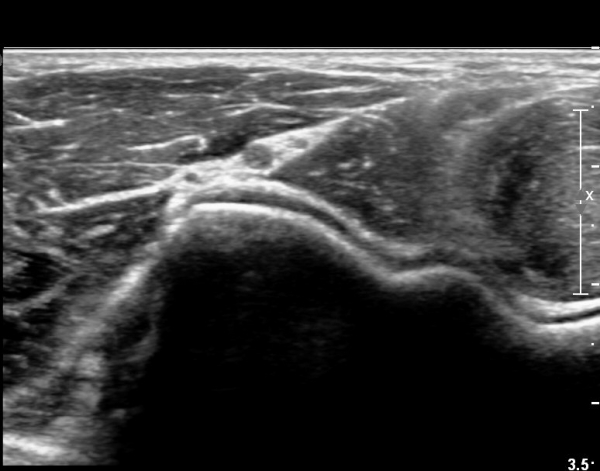

ÆÈ²ÞÄ¡ ¾Õ, Èİñ°£½Å°æ Ⱦ´Ü¸é °Ë»ç¿¡¼ Èİñ°£½Å°æÀÇ ºÎÁ¾ÀÌ °üÂûµÇ°í (»çÁø 1),